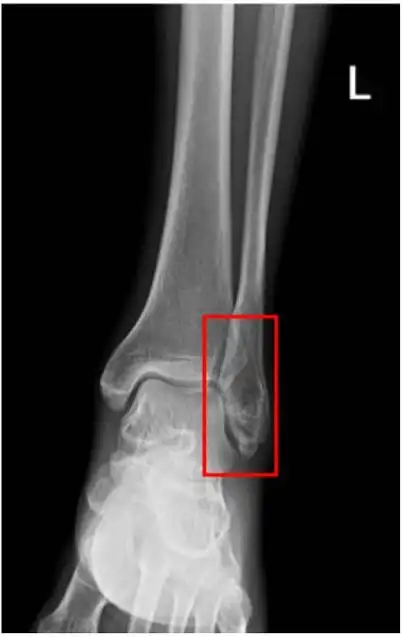

踝关节x线片或右踝关节ap和侧位片诊断踝关节骨折.

典型踝关节骨折的治疗讨论

右侧胫腓骨远端似见横行骨折透亮线,断端对位对线尚可然而,一个优秀的

脚踝(左腓骨远端)骨折月记 - 知乎